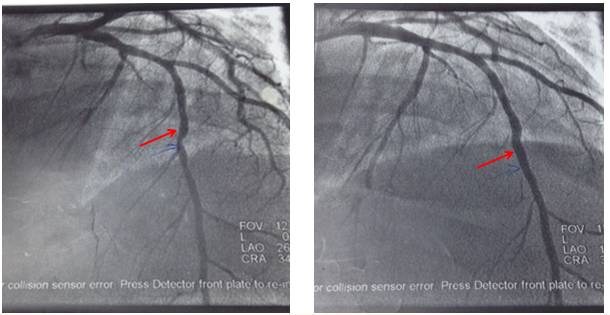

进一步检查:CAG+PCI术

造影示:LAD中段80%狭窄,植入支架一枚